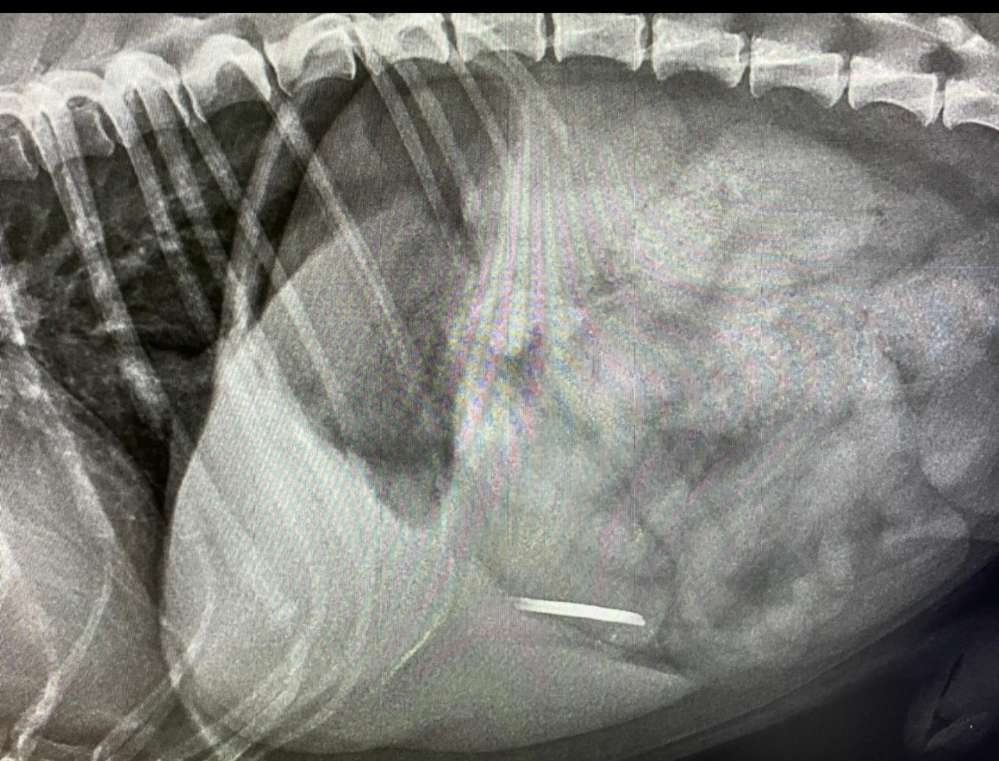

Bitte passt auf eure Fellnasen auf..

Der kleine hat einen Nagel im Darm

Und schwebt in Lebensgefahr 😧🙈